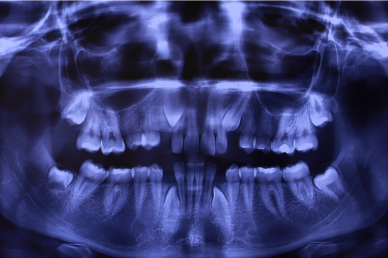

اولین قدم برای شروع درمان ارتودنسی معاینه بیمار توسط دندانپزشک ارتودنسی برای تشخیص است. علاوه بر معاینه، مدارک مورد نیاز برای ارتودنسی، عکس او پی جی و لترال سفالومتری برای بررسی زوایای ریشه ها و زوایای فک و صورت- عکسهای فتوگرافی از صورت و دهان- و اسکن داخل دهانی است. بعد از تکمیل مراحل تشخیص، دندانپزشک ارتودنسی با توجه به نیاز شما برنامه درمانی و نوع درمان مشخص میکند . و درمان شما شروع میشود

-  دندان های نهفته (که به طور جزئی یا کامل در استخوان فک شما گیر کرده اند).

کودکان باید اولین ویزیت ارتودنسی خود را حداکثر تا سن 7 سالگی انجام دهند. شاید بسیاری از کودکان در این سن نیازی به درمان ارتودنسی نداشته باشند ولی زمان خوبی است تا متوجه شوید آیا مشکلاتی وجود دارد که باید مراقب باشید یا خیر.

مهم است که کودکان و نوجوانان خود را در زمانی که هنوز در حال رشد هستند ارزیابی شوند. درمان زودهنگام ممکن است نتایجی را به همراه داشته باشد که پس از توقف رشد صورت و فک ها امکان پذیر نباشد.